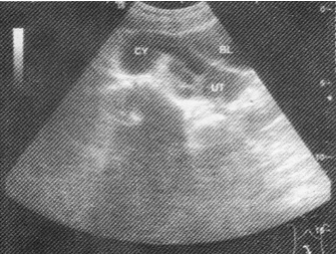

女性,26岁,下腹部疼痛数月。妇科检查右侧附件区增厚、增大,超声检查如图所示,最可能的诊断为

A.右侧卵巢黄体囊肿

B.右侧输尿管扩张

C.右侧输卵管积液

D.盆腔积液

E.右侧卵巢畸胎瘤